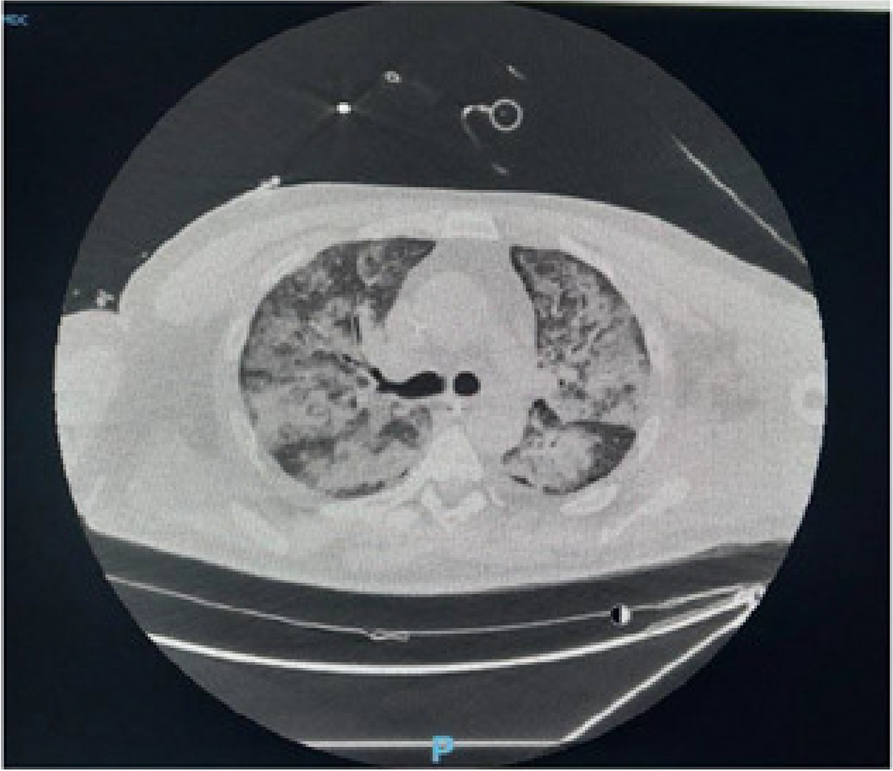

A few hours after the admission in ICU he reported a blunt abdominal pain, mainly on the right side, nausea and the exams showed increased amylase levels, urologists excluded any surgical involvement of pancreatic tissue and suspected a transient sphincter of Oddi dysfunction [3]. After one night in ICU he was transferred to the urology ward due to his clinical stability, even though Amylase peaked at 2340 U/l. Two days later abdominal pain increased to severe, with characteristics of peritonism and increased inflammatory markers. An abdomen-thorax CT scan revealed acute pancreatitis (AP) (Figure 1) and he was transferred to ICU. He started a standard treatment for acute pancreatitis and antibiotic therapy [4].

On postoperative day nine, due to general deterioration of clinical conditions and further anemization that required blood transfusion, he underwent an emergency laparotomy, in which propofol was not used as an anesthetic drug, that found a completely necrotic pancreas. The following day he faced a multi organ failure (MOF) which rapidly led to death. Consent to publish the case report was accorded by the family.

Acute pancreatitis (AP) Is a complex and severe disease with a high mortality rate [4]. Propofol, is a common anesthetic drug which is widely used in daily practice for sedations and general anesthesia [5], few cases of Propofol Induced AP have been published, in which the diagnosis has been made excluding more common causes [6].

In fact, Propofol is listed as a possible cause of AP, class Ib, based on the classification of Badalov et al. [7]. Following the scheme proposed by the systematic review by Haffar et al for Propofol induced AP [6] we could confirm that our hypothesis is plausible. He satisfied the American College of Gastroenterology criteria for AP [8,9] and it is classified as severe acute pancreatitis according to the Revised Atlanta Classification with peripancreatic necrotic fluid collection [10]. Marshall score [11] after admission was two and Naranjo et al [12] probability scale for drug adverse reaction was three, meaning that the adverse reaction is possible. Latence according to Badalov et al [7] has been short or intermediate. Exclusion of other plausible causes, timing of pancreatitis symptoms and previous cases in literature support our hypothesis of propofol induced pancreatitis.

Fig. 1 (abstract A21).

See text for description